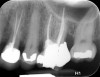

Fig 1. Preoperative radiograph showing apical bone loss.

Figure 1

Clinical procedure: If apical bone loss is present (Figure 1) a collagen/gelatin sponge (eg, Gelfoam®, Pfizer Inc., www.pfizer.com) can be placed apically so that the MTA can be delivered to the desired working length. (Any other surgical resorbable sponge would also work, such as OraPlug® [Salvin Dental Specialties, www.salvin.com], Surgifoam® [Midwest Dental, www.mwdental.com], or Surgispon® [Aegis Lifesciences, www.surgispon.com]). This is done by taking a small piece (2 mm x 2 mm) of the resorbable sponge and pushing it down to and through the root apex with an endodontic file. Once this is done, MTA is packed down the canal with a custom-fitted cone. The clinician can use a rubber stopper on the gutta-percha cone to know the exact length of MTA placed in the apical third (Figure 2). Once the apical third is sealed with 3 mm to 5 mm of MTA, the remaining coronal canal space can be back-filled using a warm gutta-percha technique (Figure 3).